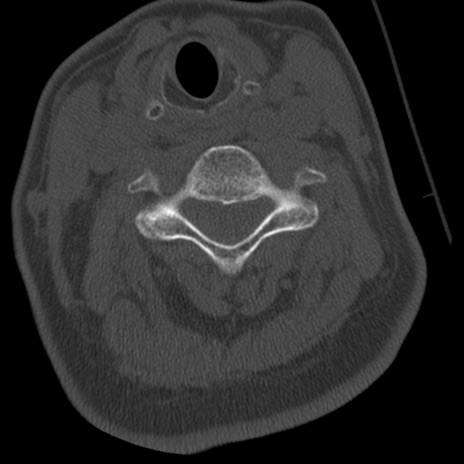

症例50 頚椎CT(横断像)

頚椎CT